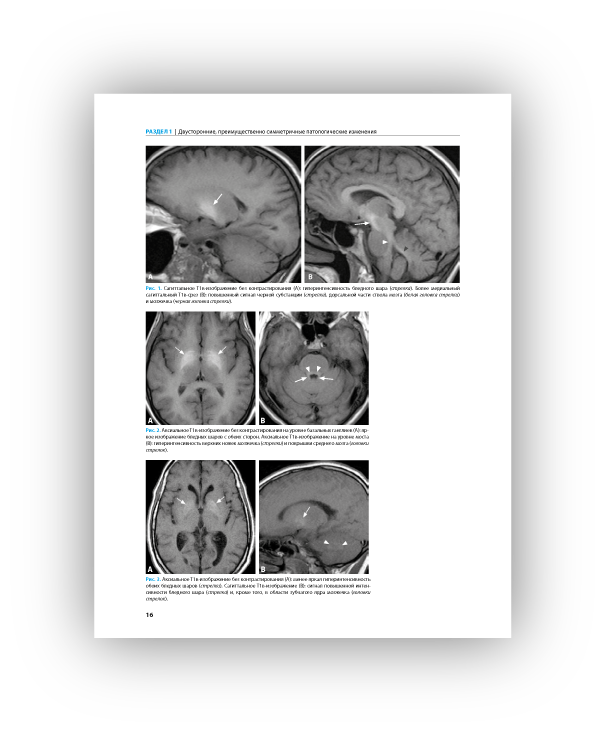

Книга построена по принципу руководства по дифференциальной диагностике, в основе ее рубрификации лежат особенности диагностических изображений. Иллюстрации размещены на разворотах слева, справа дается емкое описание наблюдаемой патологии и список для дифференциальной диагностики с указанием страниц, на которых описаны дифференцируемые состояния. В руководстве приведено более 1500 изображений (в основном компьютерных и магнитно- резонансных томограмм) головного мозга, наблюдаемых при более чем 200 заболеваниях. Книга начинается с описания картины двусторонних симметричных поражений и срединных дефектов, так как их легче всего спутать друг с другом, особенно если читатель имеет относительно небольшой опыт.